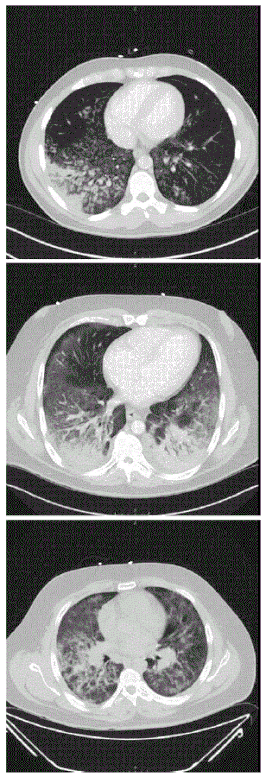

CT-scans tonen diffuse longinfiltraten bij drie patiënten met een ernstige vorm van vaping-gerelateerde longschade.

Vaping-gerelateerde longschade (VGL), in het Engels gekend als Vaping-associated pulmonary injury (VAPI), vaping-associated lung injury (VALI) of e-cigarette, or vaping, product use associated lung injury (E/VALI), is een overkoepelende term voor longziekten geassocieerd met vapen. De term verwijst vooral naar de levensbedreigende en ernstige gevallen.[1]